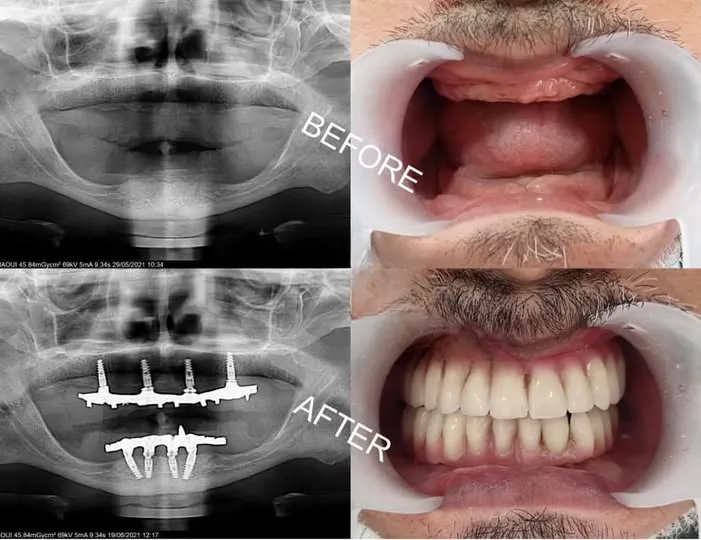

All-on-6 réhabilitation complète

All-on-6

Réhabilitation complète d'une arcade avec 6 implants stratégiquement positionnés pour une stabilité maximale et une longévité accrue, adaptée aux cas complexes et offrant un confort comparable à celui des dents naturelles.

6 implants Stabilité maximale Réhabilitation complète